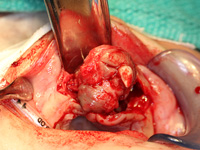

Excisional biopsy of the lesion was done under general anesthesia within hours of presentation. Fine-needle aspiration for fluid was negative. Sharp dissection of the lesion was followed by subperiosteal dissection, which revealed involvement of the vestibular and palatal cortices of the left maxillary alveolus. Both maxillary primary central incisors (erupted 61 and unerupted 51) and the unerupted left maxillary primary lateral incisor and canine (teeth 62 and 63) were excised with the lesion. Based on the clinical appearance of the tissues, the resected area was extended to include the presumed follicles of the maxillary permanent left central incisor, lateral incisor and canine (unerupted teeth 21, 22 and 23) to reduce the likelihood of the tumour's recurrence (Figs. 4, 5). Following resection, the soft tissue adjacent to the nasopalatine nerve was electrocauterized, and the surgical site was closed with a continuous vicryl suture (Fig. 6).